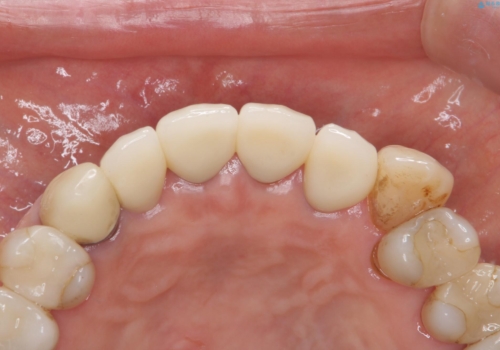

前歯のセラミック 神経の再治療から

神経の治療から念のためやり直ししてからセラミックでかぶせました。

金属の土台が入っていましたがすべて外し、ファイバーコアでやり替えています。

- 101.2万円(ジルコニアクラウン12.1万円×4 仮歯1.1万円×4 ファイバーコア2.2万円×4 精密根管治療9.9万円×4)費用は治療当時の料金となります